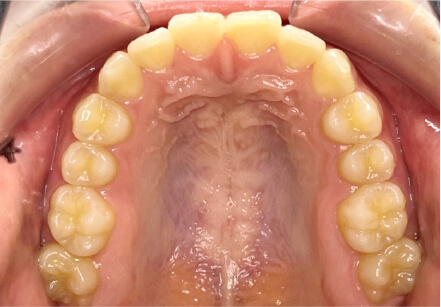

叢生の症例

9歳

/

女性

相談内容

マイオスマイルからの移行

カウンセリング・診断結果

上11捻転、上33スペース不足、インビザで歯列矯正

治療内容・方法

全額アライナー矯正 クリアコレクト

術後の経過・現在の様子

リンガルアーチ使用

治療のリスク

痛み・歯根吸収・歯肉退縮・虫歯・後戻り

費用・治療期間

(マウスピース矯正のみ)440,000円+220,000円 月々27,500円、9ヶ月+myo1年10ヶ

トレーニングなど